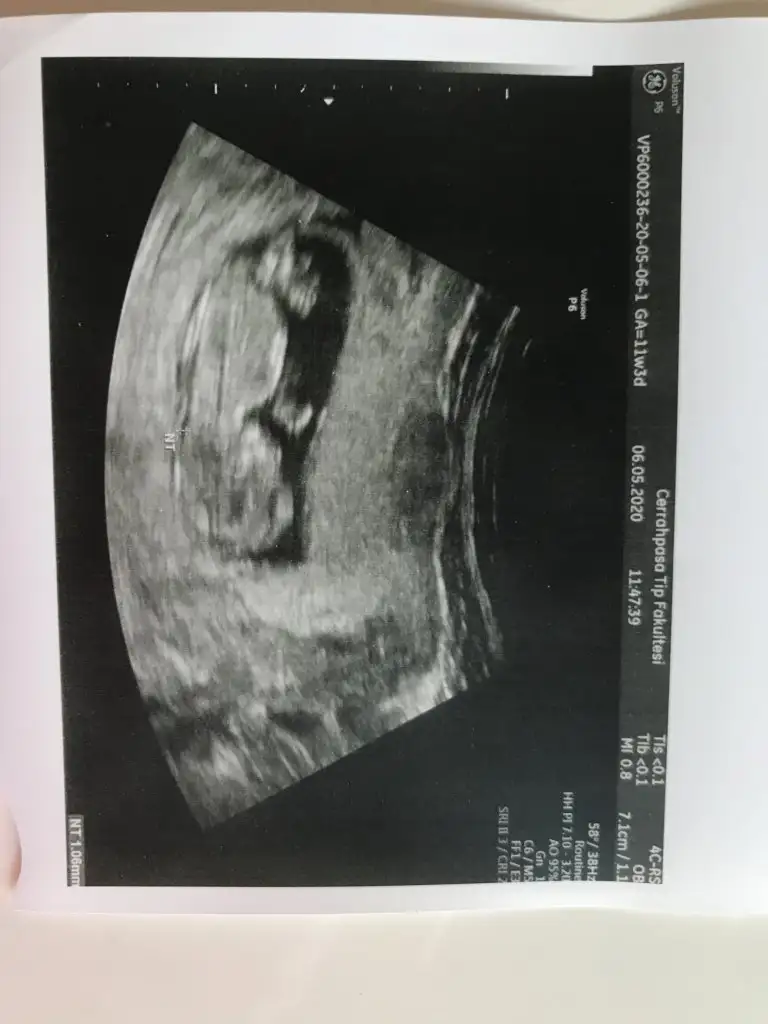

Hiç net değilNet olmayanlarıda tekrar cektim bidaha onlar 13 hafta diğerleri 11 hftalık

Aynen daha iyi ise usg net tahmin edilirEn net olan buydu ama yarın tekrar kontrolüm var 12+4 olacak olmazsa onu atarım![]()